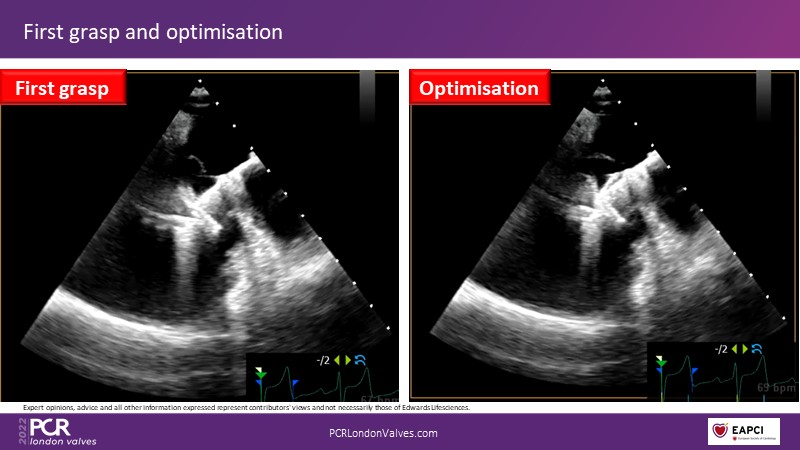

The new PASCAL Precision system unleashes the full potential of mitral transcatheter edge-to-edge repair

Join this panel of experienced physicians to learn more about the novel PASCAL Precision system and to discuss implant selection and clinical data. Finally, participate in a recorded case demonstrating the use of the PASCAL Precision system for the treatment of mitral regurgitation.